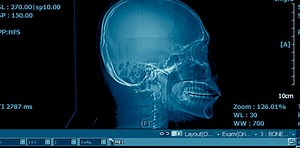

Craniosynostosis - Mayo Clinic